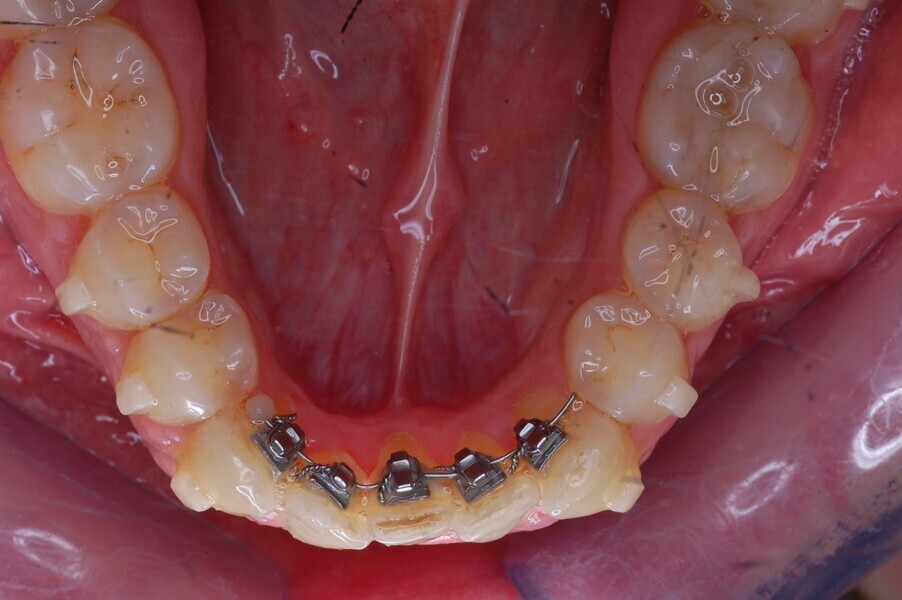

Fig. 37–44: Sequential intra-oral photographs illustrating progressive alignment of the mandibular arch.

Fig. 38.

Fig. 39.

Fig. 40.

Fig. 41.

Fig. 42.

Fig. 43.

Fig. 44.